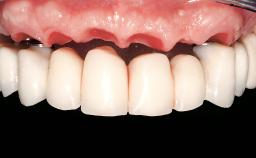

Conventional Loading of Eight Implants in the Maxilla and Final Restoration with a Full-Arch Gold-Ceramic FDP

A 35-year-old Caucasian female presenting with advanced periodontal disease involving both the maxillary and the mandibular dentition was referred for evaluation. The patient, a non-smoker in good general health, requested treatment for recurrent periodontal abscesses, tooth mobility, and discomfort during chewing, as well as restoration of her missing teeth with a fixed prosthesis to improve mastication and esthetics. All residual maxillary teeth exhibited plaque deposits, deep pockets, bleeding on probing, and class III mobility and were evaluated as hopeless. All residual mandibular teeth except tooth 37 could be maintained after periodontal therapy.